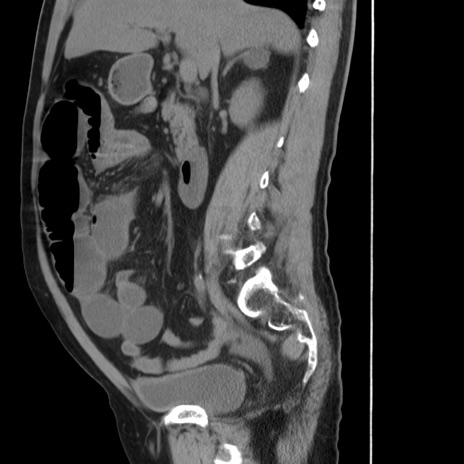

症例20(矢状断像)

【症例】 60歳代男性

【主訴】 腹部膨満、嘔吐

【現病歴】5日前頃より倦怠感を認め食事量減少し4日前の朝嘔吐、食事摂取困難となった。 3日前近医受診し点滴施行され整腸剤などを処方された。 当日他院を受診し、腹部膨満著明、炎症反応の上昇(CRP10.8、WBC11200)あり、紹介受診となる。

【身体所見】 意識JCS1 受け答えがはっきりしないBP 111/57mHg、 P 67bpm、、BT35.2°C、SpO2 97%(RA)、 腹部:膨隆、打診で鼓音あり、全体的に圧痛有り、腸蠕動音(-)、反跳痛ははっきりせず。

【データ】WBC 11400、CRP 14.20